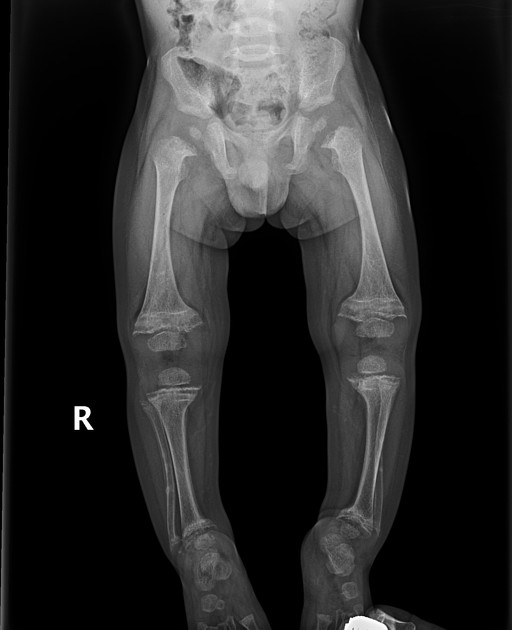

What is the most common symptom of rickets?

Bowed legs.

What is the best imaging modality to diagnose rickets?

Plain X-rays.

What is seen on X-rays of a rickets patient?

Bowed legs and widened wrists due to metaphyseal cupping.

What causes the widening at the metaphysis in rickets?

Accumulation of non-mineralized bone tissue.